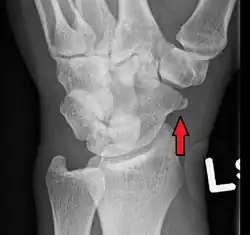

Scaphoid pseudarthrosis, before and after treatment with Herbert screw.

Treatment of scaphoid fractures is guided by the location in the bone of the fracture (proximal, waist, distal), displacement (or instability) of the fracture, and patient tolerance for cast immobilization.